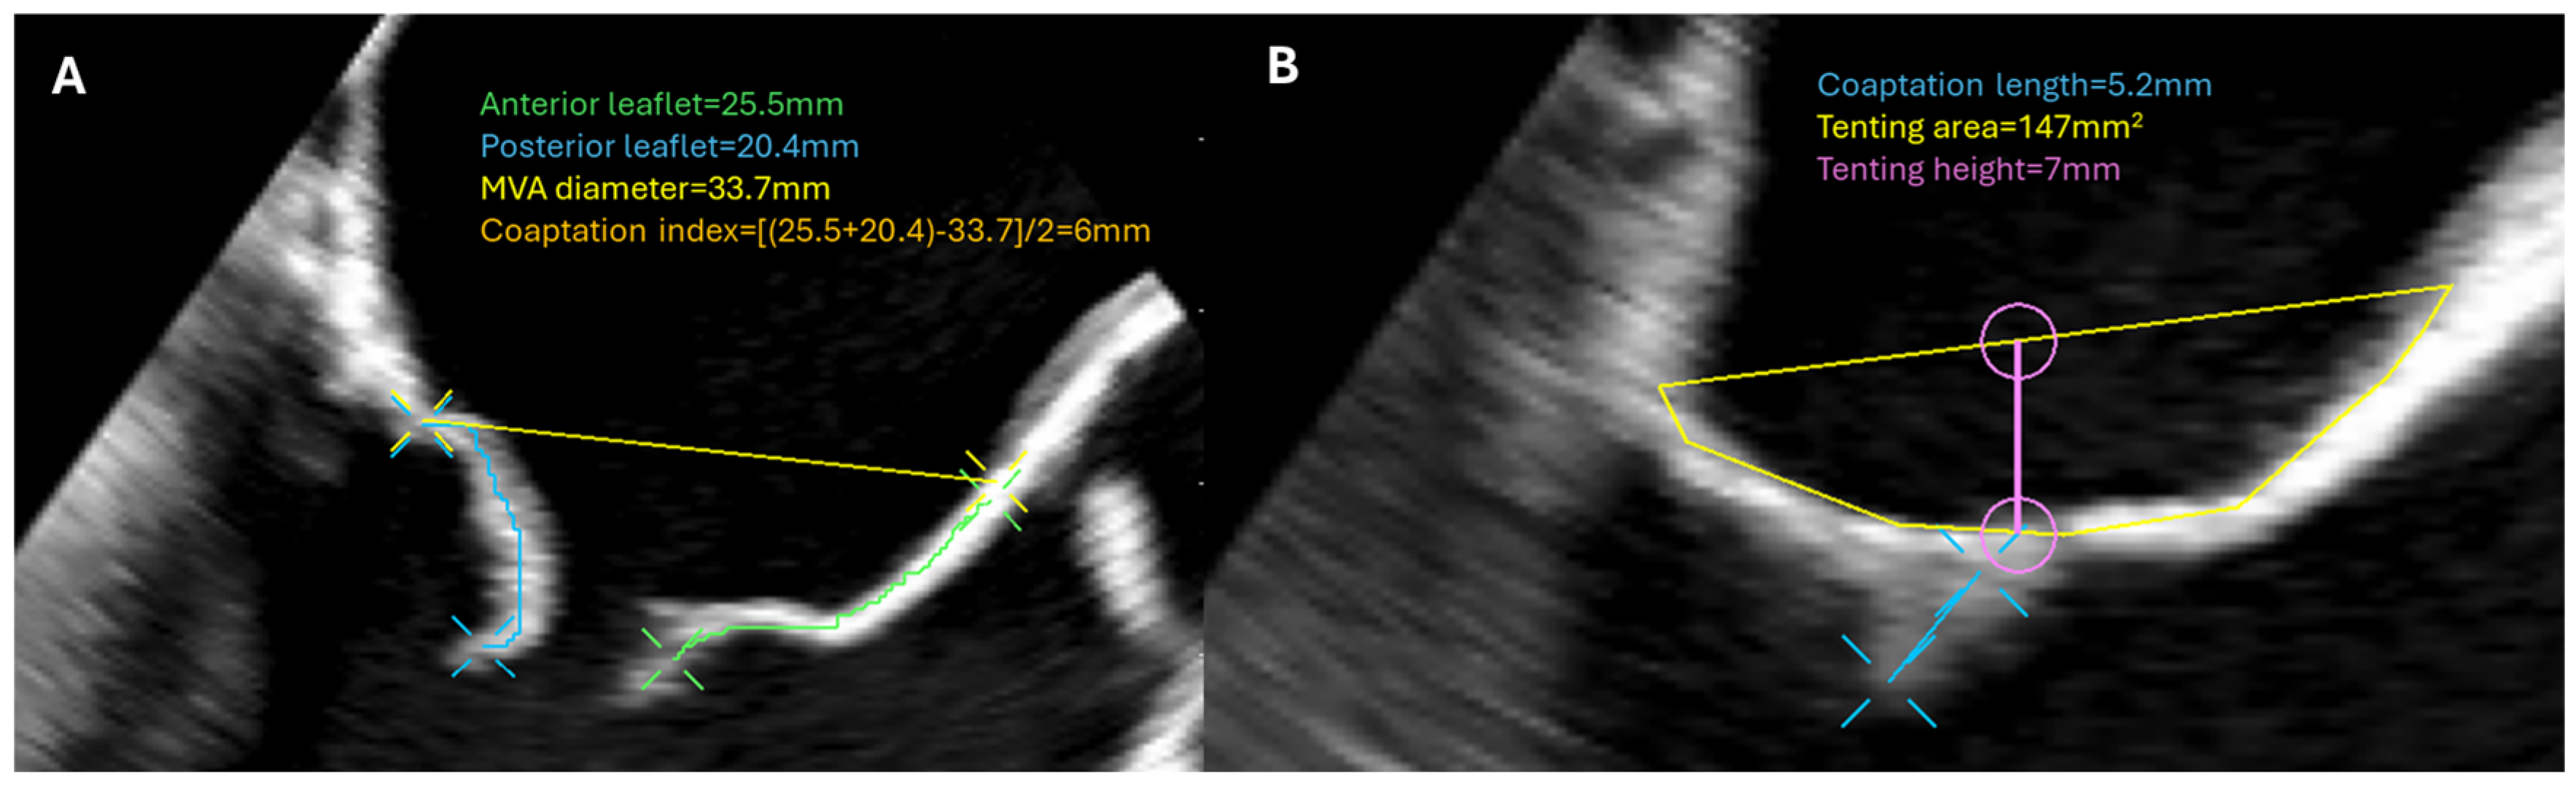

3. Mitral Valve Disease

| MV repair | Describe MR mechanism Measure leaflet length Measure annulus size Estimate MR severity | Ensure sufficient MR reduction No flail part Exclude iatrogenic MV stenosis |